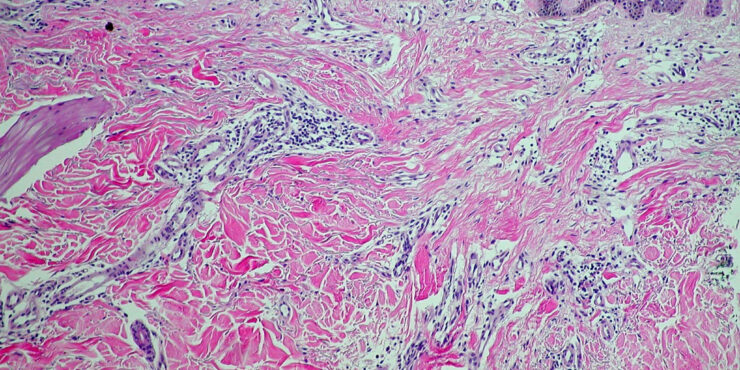

malignant-fibrous-histiocytoma